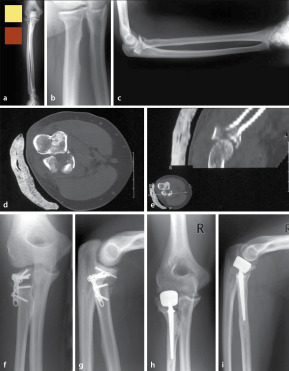

• Swiss Medical Forum Die Kindliche Monteggia Lasion

Proximaler Unterarm Springerlink Reinhold Naegele